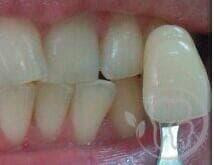

Фролова Инга Михайловна: портфолио (5)

Наращивание зубов